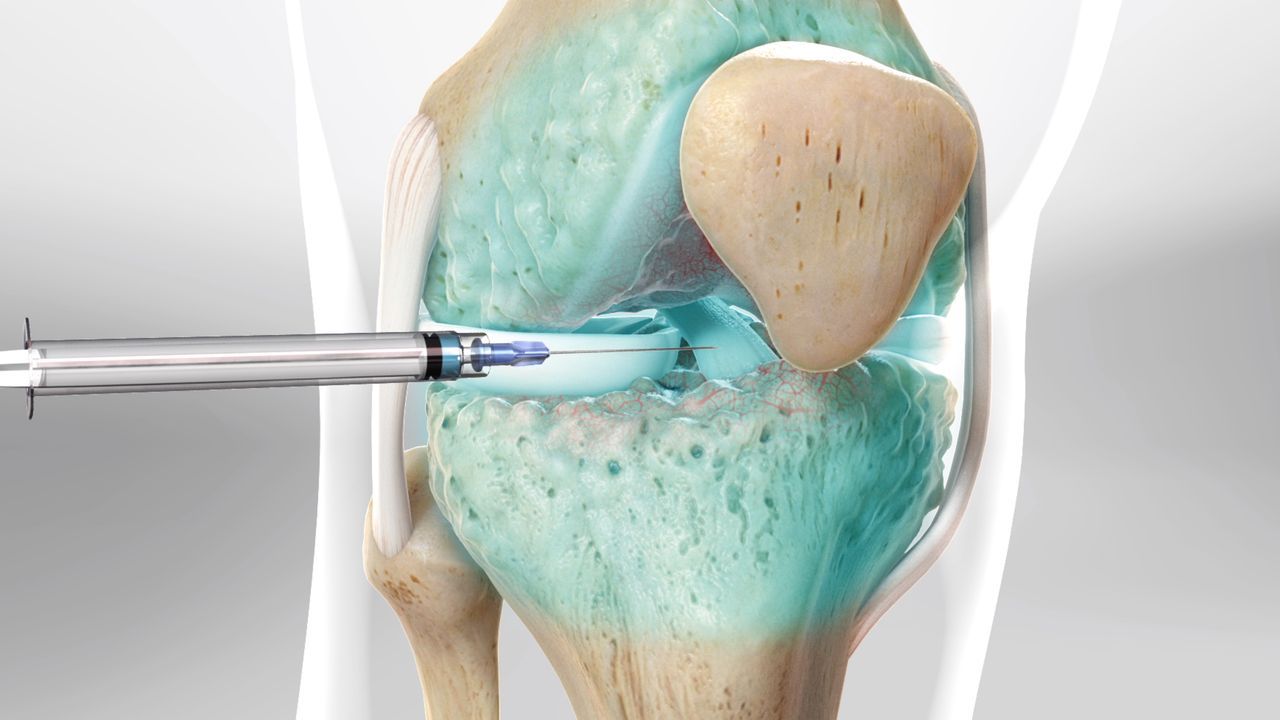

Η οστεοαρθρίτιδα γόνατος αφορά την καταστροφή του αρθρικού χόνδρου, του προστατευτικού δηλαδή εκείνου ιστού που αμβλύνει τις τριβές μεταξύ των οστών και βοηθά στην κύλιση και ολίσθηση των αρθρώσεων.

Όταν ο αρθρικός χόνδρος φθαρεί και στα δύο γόνατα μια τεχνητή πρόθεση παίρνει την θέση του. Η χειρουργική τεχνική της εμφύτευσης της προθέσεως και την 2 αρθρώσεων στον ίδιο χρόνο ονομάζεται Bilateral Knee Replacement – Αμφοτερόπλευρη αρθροπλαστική γονάτων.

Θεραπεία οστεοαρθρίτιδας με υαλουρονικό οξύ